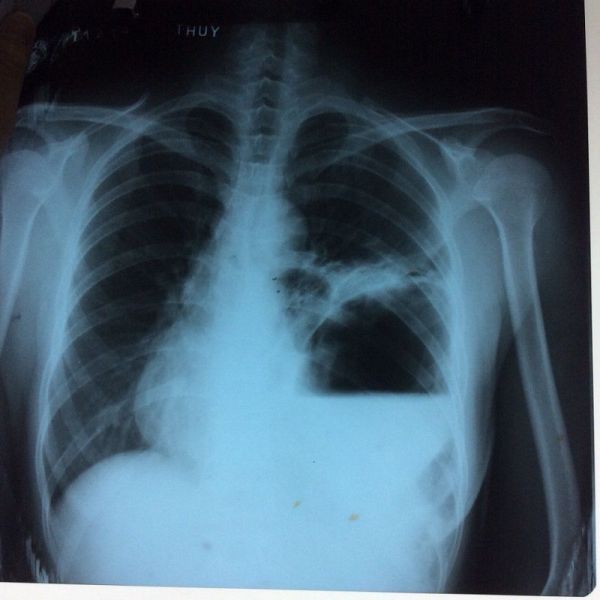

Thoát vị hoành trái và thoát vị dạ dày

Trên đây là một số thông tin và hình ảnh về bệnh Thoát vị hoành trái và thoát vị dạ dày, hy vọng sẽ giúp các bạn có những hiểu biết cơ bản để đề ra hướng chẩn đoán và điều trị bệnh phù hợp!